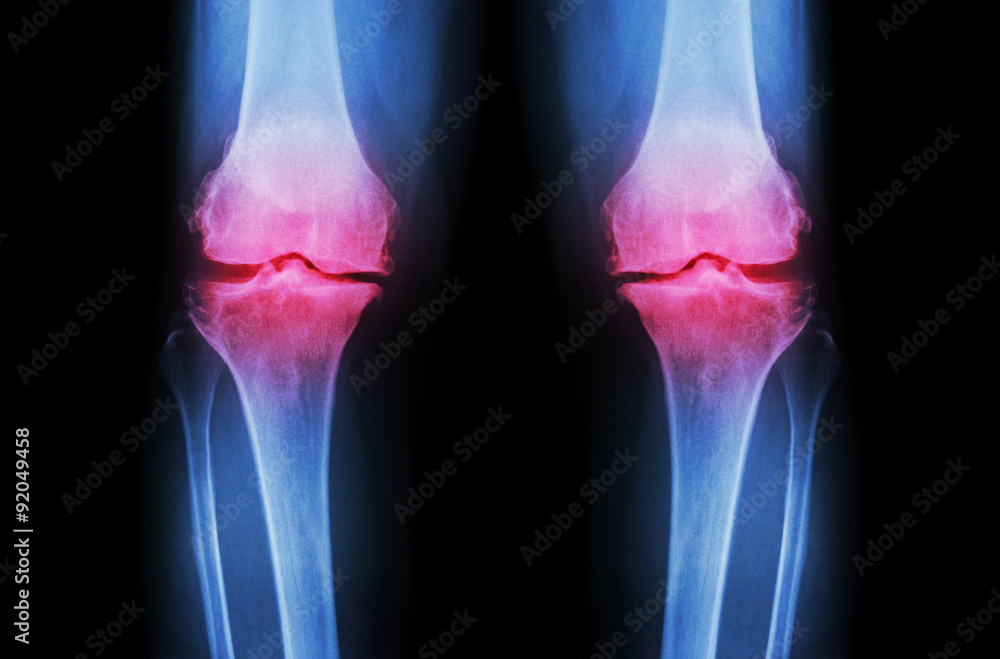

Osteoarthritis Knee ( OA Knee ). Film Xray Both Knee ( Front View ) Show Narrow Joint Space Joints Cartilage Loss It happens when the cartilage that lines your joints is worn down or damaged. — osteoarthritis occurs when the cartilage that cushions the ends of bones in your joints gradually deteriorates. — stage 4. — cartilage in the knee can wear down over time. When this happens, you may need. The goal of cartilage restoration procedures is. Joints Cartilage Loss.

Osteoarthritis Knee ( OA Knee ). Film xray both knee ( front view ) show narrow joint space Joints Cartilage Loss There are four stages of osteoarthritis (oa): Eventually, you may have no cartilage left in your knee. damaged cartilage can also lead to arthritis in the joint. It happens when the cartilage that lines your joints is worn down or damaged. — cartilage in the knee can wear down over time. — stage 4. When this happens,. Joints Cartilage Loss.

Osteoarthritis Knee ( OA Knee ). Film xray both knee ( front view ) show narrow joint space Joints Cartilage Loss There are four stages of osteoarthritis (oa): — stage 4. It happens when the cartilage that lines your joints is worn down or damaged. Early, mild, moderate, and severe. You can also be diagnosed with a stage called pre. When this happens, you may need. damaged cartilage can also lead to arthritis in the joint. Eventually, you may. Joints Cartilage Loss.